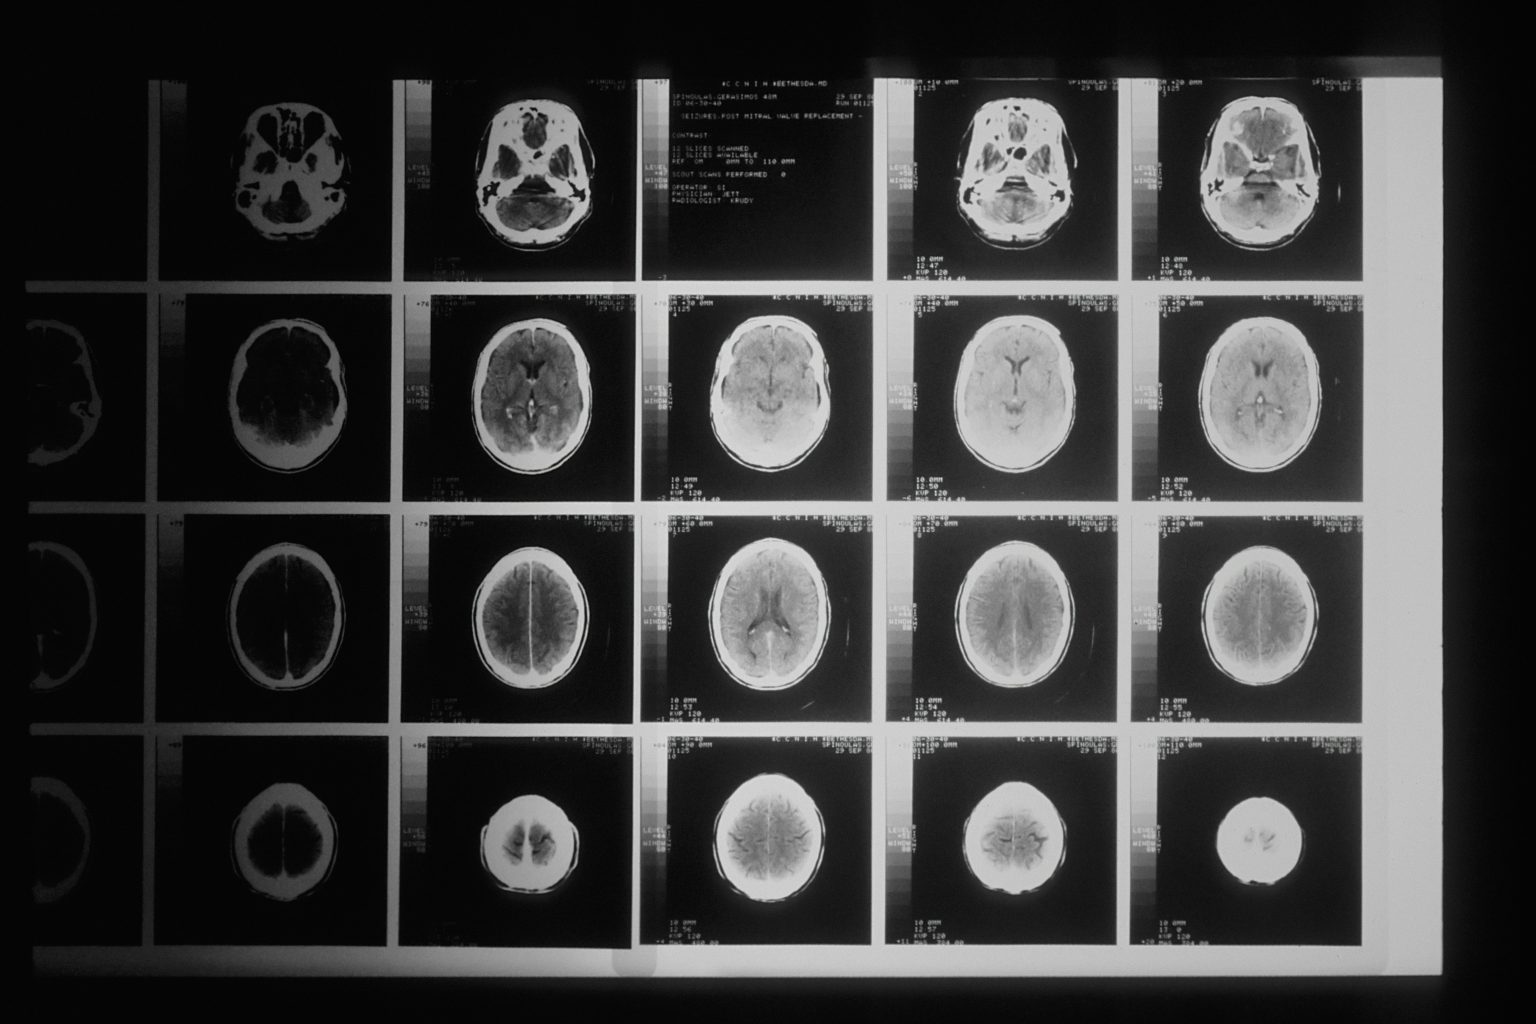

使用對比增強磁振造影(MRI)預測對鉑類化合物無效之頭頸鱗狀細胞癌患者的存活率

對鉑類化合物無效(Platinum-refractory)的頭頸鱗狀細胞癌患者其預後相當不佳。即便使用免疫檢查點療法(Immune Checkpoint Therapy),其整體存活期(Overall Survival, OS)仍然只有7.7個月。